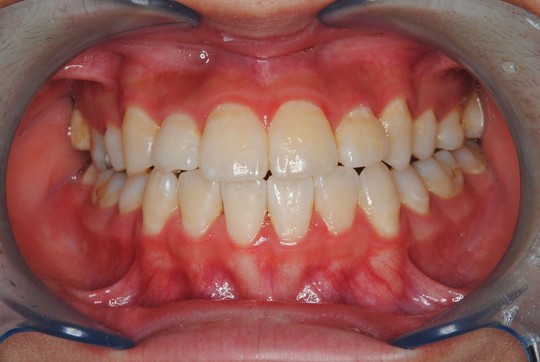

治療後

気になっていた前歯のガタガタも改善され綺麗な歯並びになりました。

お口の模型とレントゲン写真をもとにした術前診査から、上下の顎の成長が弱く歯の大きさに対して顎が小さいため、本来並ぶべき場所に歯が並ぶことができないことから歯列不正が生じていることがわかりました。治療内容としては、顎の成長促進、歯列拡大床による歯列弓の拡大を目的として床拡大装置を使用した治療を行いました。